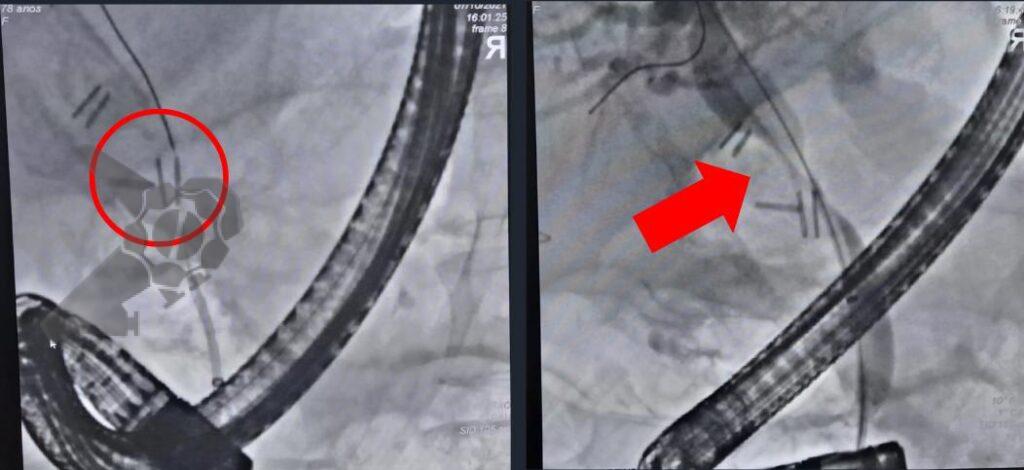

Diante desse cenário, foi indicada terapêutica minimamente invasiva combinada de Colangiopancreatografia retrógrada endoscópica (CPRE) para drenagem da via biliar e drenagem percutânea através de radiologia intervencionista para o bilioma. Ambos bem sucedidos, entretanto CPRE revelou lesão iatrogênica da via biliar (clipagem parcial do ducto colédoco) e coledocolitíase proximal à subestenose, tendo sido procedida drenagem da via biliar com prótese plástica (Fig 3). A drenagem percutânea foi guiada por USG (Fig 4) e aspirado 100ml de liquido bilioso, mantido dreno por 3 dias sem intercorrências.

Paciente manteve assintomática e acompanhamento ambulatorial para programação de tratamento definitivo, que foi optado pela dilatação da via biliar (balão CRE 6-8mm) e inserção de prótese metálica auto-expansível totalmente recoberta (10 x 80mm) (Fig 5). O procedimento foi realizado 90 dias após a primeira CPRE sem intercorrências e optado pela retirada após 1 ano. A última CPRE foi realizada 12 meses após a inserção da prótese metálica no qual foi possível retirá-la, extrair o cálculo da via biliar proximal e obter uma colangiografia sem sinais obstrutivos ou extravazamentos ao final do procedimento (Fig 6).